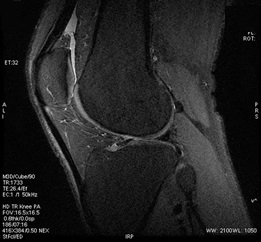

Figure 1. Knee example with User CV 12 set to 30 degree flip angle

- A larger flip angle increases the SNR with a tradeoff of increased image blurring.